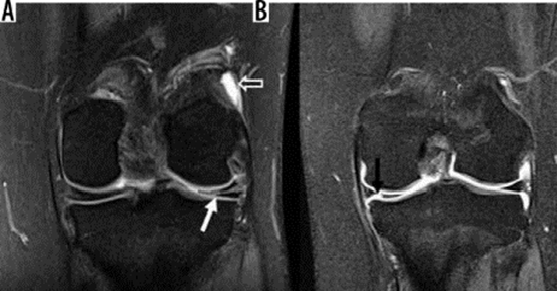

Hình 7. Vết rách ngang sụn. Hình ảnh pd coronal xóa mỡ với tín hiệu tuyến tính trong sụn (mũi tên đóng) kéo dài đến mặt dưới của thân sụn bên, phù hợp với vết rách. Tín hiệu cao (mũi tên mở) ở mặt ngoài, mặt sụn giữa không kéo dài đến bề mặt tạo hình sụn và phù hợp với thoái hóa niêm mạc.

Hình 9. Rách sụn chêm và mô hạt đang lành sau mổ. A là hình ảnh T1 xóa mỡ sau khi tiêm thuốc tương phản trong khớp với tín hiệu tuyến tính sụn chêm bên có giá trị trung gian về cường độ tín hiệu (mũi tên trắng), so với chất tương phản sáng được tiêm vào không gian khớp (mũi tên mở), có thể đại diện cho mô hạt trong sụn chêm bên đã được phẫu thuật sửa chữa trước đó. B là hình ảnh T1 xóa mỡ sau khi tiêm thuốc tương phản nội khớp cho thấy khiếm khuyết cường độ sáng tương phản (mũi tên đen) ở sụn chêm giữa, biểu thị vết rách xuyên tâm.